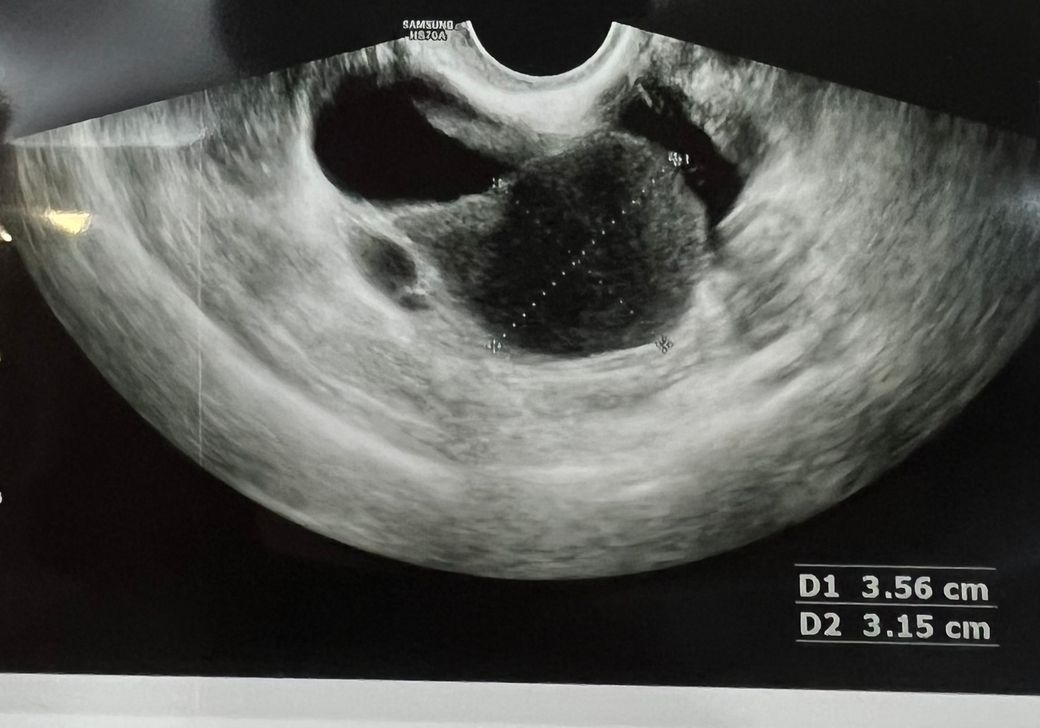

자궁내막종같다고 하시는데 다른 것일 수 있는지 봐주 실 수 있나요?

자궁내막종이라고 선생님이 그러셨고 의심하는게 아니라 아닐거라고 믿고 싶은 마음에 한번 올려보아요 원래 제가 출혈성 황체낭종이 자주 생기는데 이 회색 부분이 황체낭종때문에 피가 고인 것 일 수 있는건지 궁금합니다 자궁내막종이 확실한가요? 사라질 확률은 없는걸까요? 비잔정 먹기가 너무 두렵습니다

초음파로 조직학적인 진단을 하는 것은 어렵습니다.

환자분이 원하시는 것처럼 출혈성 황체 낭종과 자궁내막종을 감별하는 것 역시 어렵습니다

초음파 영상으로는 자궁부속기에 낭종성병변이 있으며 벽은 상대적으로 균일하고 내부에 별다른 격자는 없으며

다양한 에코를 동반하고 있습니다.

출혈성황체낭종은 일단 생리하는 동안 생기는 경우가 많습니다. 그리고 낭종벽이 두껍고 불규칙한

경향이 있습니다. 자궁내막종은 초음파 소견이 다양해서 어느것이 특징적이라고 말하시는 어렵지만

내부 에코가 다양할 수 있다는 특징이 있습니다.

따라서 이를 고려하면 환자분의 병변의 경우 자궁내막종의 가능성이 더 있을 것으로 생각이 됩니다.